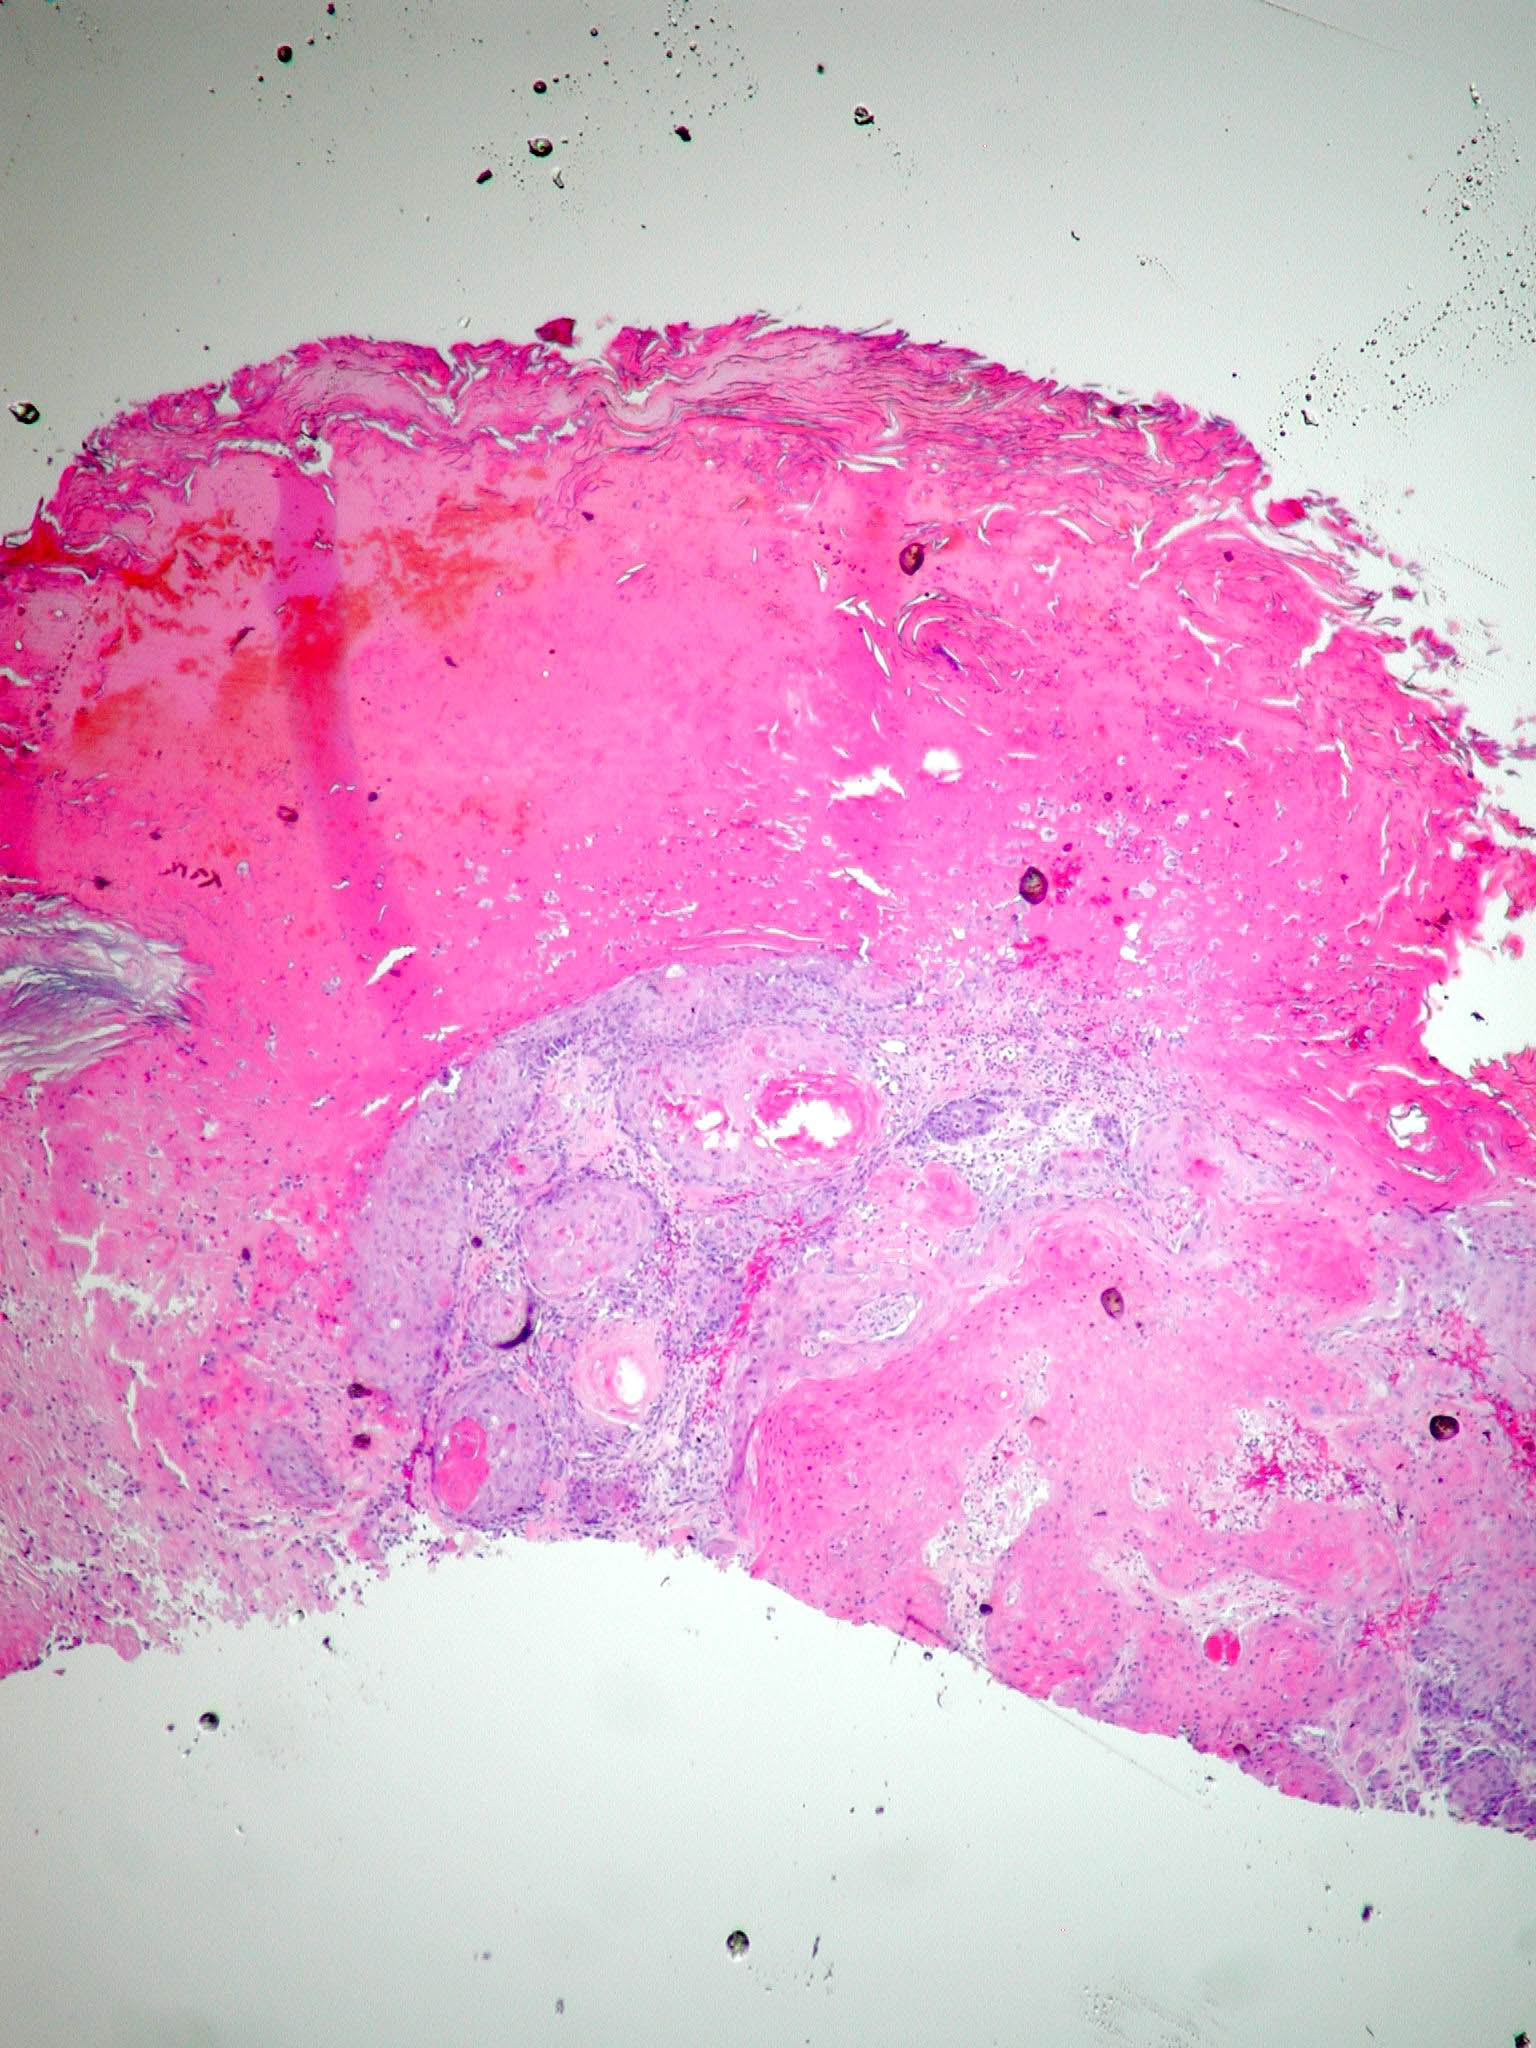

Squamous Cell Carcinoma = الكارسينوما شائكة الخلايا

OLYMPUS DIGITAL CAMERA